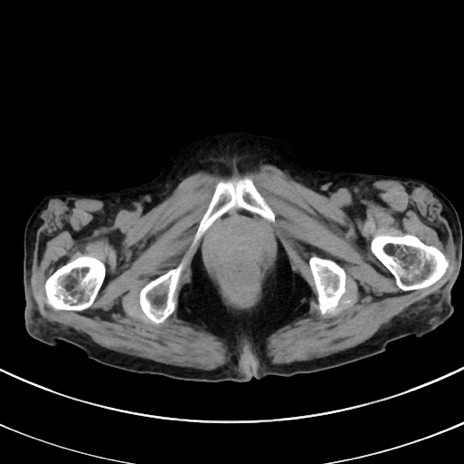

症例33(横断像)

【症例】70歳代 女性

【主訴】心窩部痛

【現病歴】延髄病変の精査・加療にて神経内科入院中。本日より心窩部痛あり。

【既往歴】虫垂炎

【身体所見】右下腹部を中心に圧痛と反跳痛あり。

【データ】WBC 10900、CRP 0.02